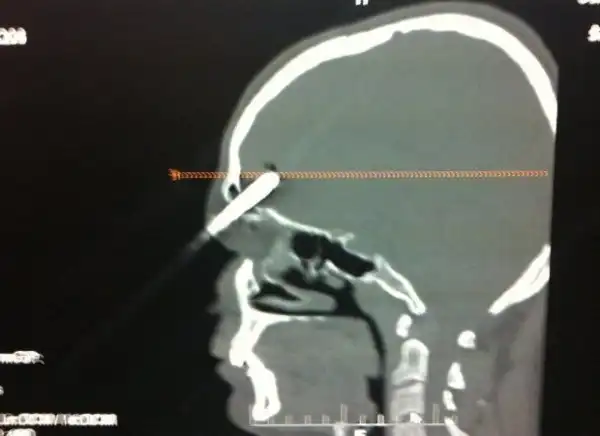

Мужик вогнал себе в мозг отвертку, закурил и отправился в больницу

25-летний поляк трудился у себя в саду, когда потерял равновесие и упал на инструменты. Поднявшись и придя в себя он посмотрел в зеркало и обнаружил, что у него из головы торчит отвертка. Мужик не стал суетиться, а просто достал сигарету, закурил и отправился к соседу, чтобы тот помог ему добраться до больницы. Как оказалось, отвертка вошла в мозг на пять сантиметров, но очень удачно, поэтому инструмент без труда извлекли, а дырку залатали.